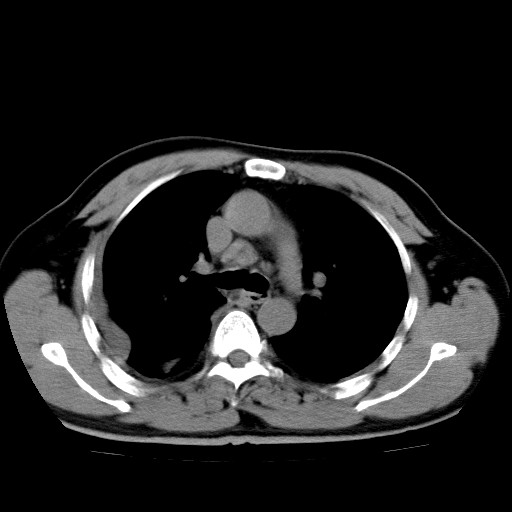

男,54岁,咳嗽,右侧胸痛10天。肺窗>150k,传不了

右肺中心型肺癌并右下肺不张,右侧胸膜纵隔转移。

右中央型肺癌并右肺下叶不张,纵隔内及右胸膜转移,右胸腔积液

考虑   右肺癌伴右下肺部分不张,阻塞性肺炎,纵隔淋巴结增大,右侧胸腔积液其他待排

考虑右肺下叶中央型肺癌并右肺下叶不张,纵隔淋巴结内及右胸膜转移。建议增强。

右下叶大片实变,肺门未见明显肿块影。有胸腔积液和纵隔内肿大淋巴结影。没有增强和肺窗,不好定。

考虑:1、右下叶周围型肺癌伴胸膜、纵隔淋巴转移?

右下叶大片性阻塞性肺炎,肺门未见明显肿块影,纵隔内可见肿大淋巴结影,右见右侧胸腔积液及右侧胸膜增厚。

考虑:右侧中心性肺癌?伴纵隔淋巴结转移。建议上传肺窗。